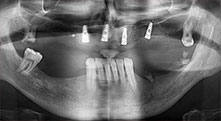

Pr Bratu : Nous utilisons couramment les instruments pour le prélèvement des blocs osseux et le clivage de la crête alvéolaire. Nous utilisons également les scies B6/B7 Piezomed pour l'ostéotomie des dents endommagées et l'extraction des implants défaillants. Bref, toutes les indications qui nécessitent des coupes profondes et propres.

Pr Bratu : Nous préférons prélever l'os sur la crête oblique externe de la mandibule postérieure, et non dans la région interforaminale. Après l'incision des tissus mous, nous utilisons les nouvelles scies pour définir la quantité d'os à prélever. De la même manière, nous les utilisons également pour la totalité de la préparation dans presque 80 % des cas. Nous avons également parfois recours à d'autres instruments piézoélectriques et, pour terminer, à un burin pour mobiliser le bloc. Nous trouvons cette technique chirurgicale très efficace.

Pr Bratu : Nous avons volontiers recours à la technique sandwich pour les augmentations mandibulaires latérales. La préparation d'un couvercle osseux est réalisée à l'aide de la scie piézoélectrique et le fragment crestal est fixé à l'aide de microvis. Nous plaçons un mélange de matériau de substitution osseuse autologue et xénogénique entre les deux. Cela fonctionne très bien. Il faut toujours s'assurer que les coupes verticales aient des dimensions suffisantes lors du clivage de la crête alvéolaire dans la mandibule. Sinon, l'os risque de se casser facilement.

Pr Bratu : J'estime que la chirurgie piézoélectrique a fait faire un grand bon en avant à la chirurgie orale. Grâce à cette technique, la préparation osseuse est plus sûre et plus facile. Par exemple, les extractions entraînent une perte osseuse minime. C'est très important d'un point de vue esthétique, surtout si la pose d'implants est prévue immédiatement.